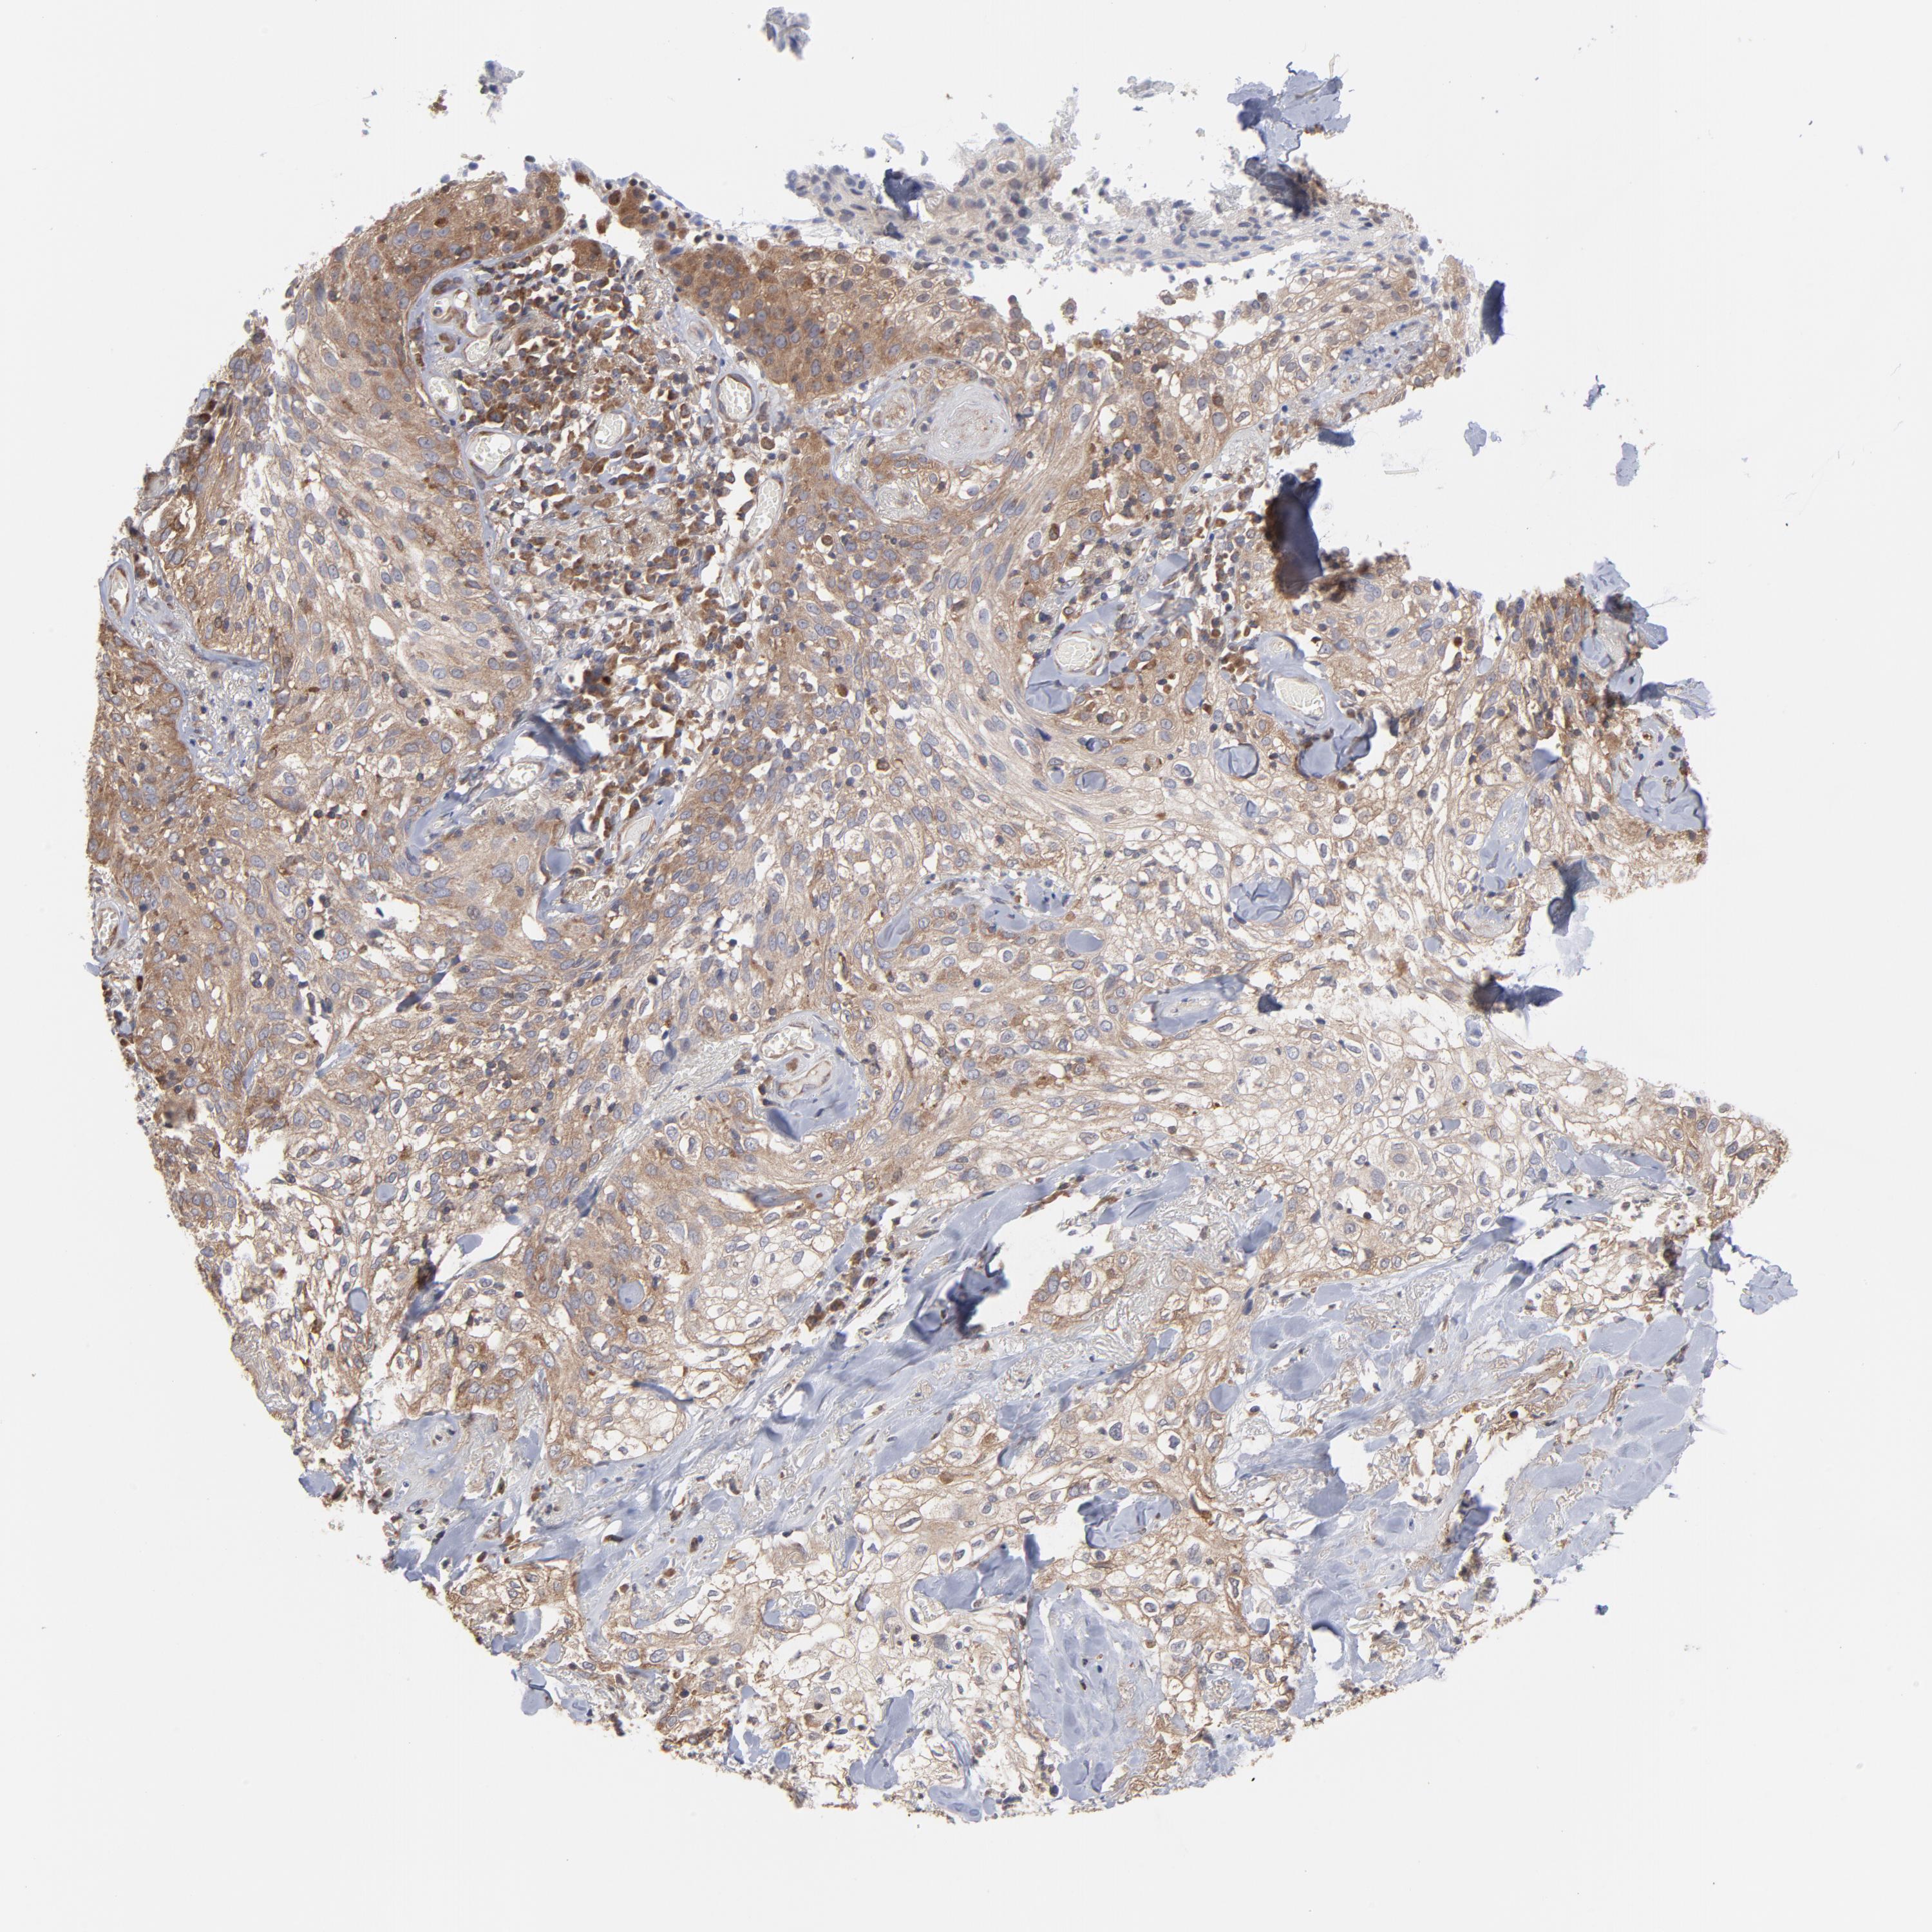

SKIN CANCER - Protein expressioni

A mouse-over function shows sample information and annotation data. Click on an image to view it in a full screen mode. Samples can be filtered based on level of antibody staining by selecting one or several of the following categories: high, medium, low and not detected. The assay and annotation is described here.

Antibody staining in the annotated cell types in the current human tissue is reported as not detected, low, medium, or high, based on conventional immunohistochemistry profiling in selected tissues. This score is based on the combination of the staining intensity and fraction of stained cells.

Each image is clickable and will lead to virtual microscopy that enables deeper exploration of all samples and also displays staining intensity scores, fraction scores and subcellular localization as well as patient and tissue information for each sample.

Antibody HPA003600

Staining

High

Medium

Intensity

Strong

Moderate

Quantity

>75%

75%-25%

Location

Cytoplasmic/membranous

Squamous cell carcinoma, NOS

Basal cell carcinoma